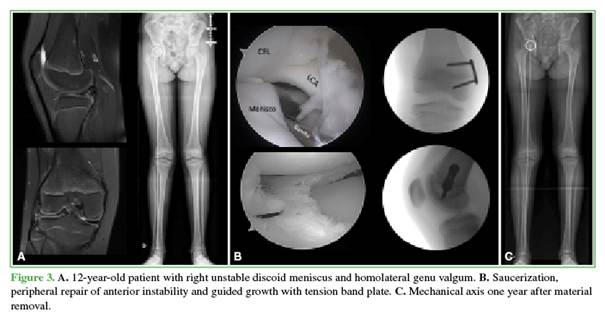

The mechanical axis is assessed at follow-up visits every 3 months. Once a slight overcorrection is achieved (Stevens zone -1),11 removal of the hardware is scheduled. One year after removal, a telemetric assessment is performed to rule out a rebound effect (loss of axis correction due to remaining skeletal growth) (Figure 3).

This article provides information on the surgical technique used by the authors for discoid meniscus preservation surgery in combination with guided growth in patients with open physes. The surgical technique described involves saucerization of the external discoid meniscus, its repair in the presence of injury or peripheral instability, as well as the incorporation of guided growth during the same surgical procedure, using either tension band plates or transphyseal screws.

Genu valgum is an angular deformity that may initially present in association with a discoid meniscus or may develop following surgical treatment of this condition. Several studies have observed a significant increase in knee valgus following partial resection of the external discoid meniscus in patients with otherwise normal lower limb alignment. A greater increase in the angle of deviation appears to correlate with the extent of meniscus resected, suggesting increased load distribution in the lateral compartment.9 The effect of lower limb alignment on the risk of developing osteoarthritis has been studied and identified as an independent long-term risk factor.15 Overloading of the lateral compartment increases stress on joint structures, which may accelerate articular degeneration and contribute to symptom recurrence. In the context of discoid meniscus—an abnormally shaped meniscus with histological alterations that predispose it to injury—16 induced or aggravated genu valgum following surgery not only compromises normal knee biomechanics but may also contribute to surgical failure. Therefore, correction of lower limb alignment may be important for improving postoperative outcomes and reducing the reintervention rate.

Historically, angular limb deformities have been corrected by osteotomy. Although effective, osteotomy is an invasive procedure requiring prolonged recovery and carrying risks of complications such as infection, delayed bone healing, and the need for postoperative immobilization.17 In recent decades, the development of guided growth techniques has revolutionized the management of these deformities in patients with open physes. Techniques such as the use of extraphyseal tension band plates18 or transphyseal screws9 allow the natural growth of the limb to be modulated, gradually guiding it into correct alignment. Unlike osteotomy, guided growth is minimally invasive, reducing recovery time, postoperative discomfort, and the risk of complications. Consequently, guided growth has become the treatment of choice for angular deformities in the pediatric population, minimizing the need for invasive interventions and offering a safe and effective alternative.4